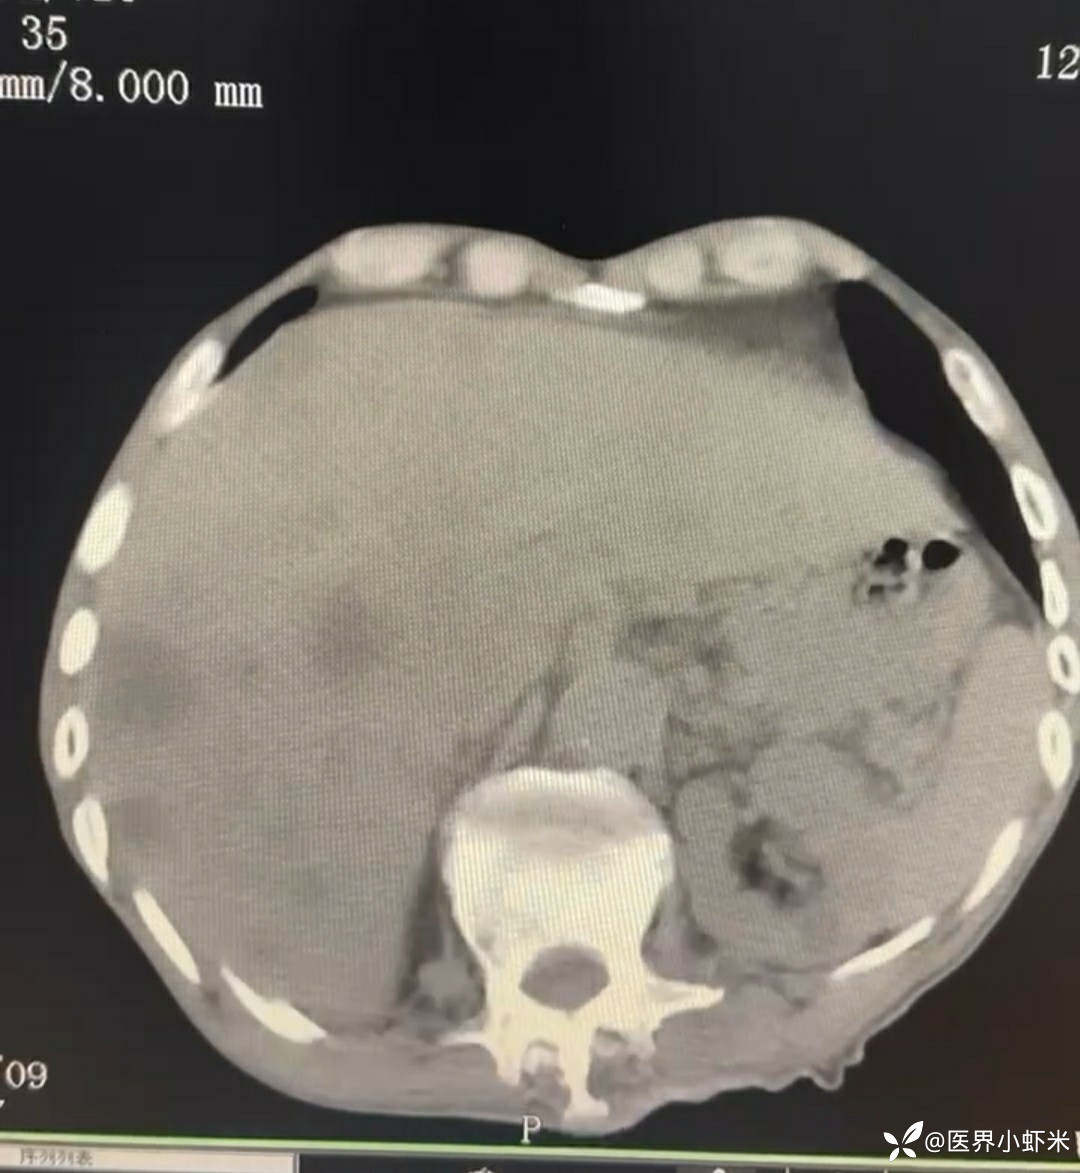

目前考虑:1.中央型肺癌伴2.肝继发恶性肿瘤?2.左丘脑继发恶性肿瘤?3.左丘脑出血?4.肾功能不全5.肝功能异常6右肾萎缩7.肺部感染8.慢性阻塞性肺病7.高血压3级(极高危)。